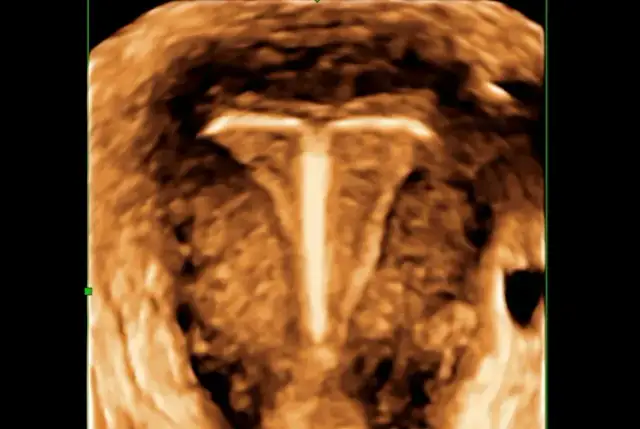

Przesunięcie wkładki domacicznej objawy – co powinno Cię zaniepokoić?

Zobacz, jakie są objawy przesunięcia wkładki domacicznej. Dowiedz się, kiedy należy skontaktować się z lekarzem i jak dbać o zdrowie reprodukcyjne.